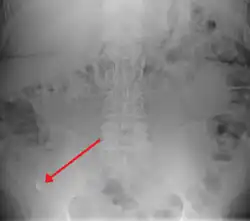

X-ray

In general, plain abdominal radiography (PAR) is not useful in making the diagnosis of appendicitis and should not be routinely obtained from a person being evaluated for appendicitis.[70][71] Plain abdominal films may be useful for the detection of ureteral calculi, small bowel obstruction, or perforated ulcer, but these conditions are rarely confused with appendicitis.[72] An opaque fecalith can be identified in the right lower quadrant in fewer than 5% of people being evaluated for appendicitis.[48] A barium enema has proven to be a poor diagnostic tool for appendicitis. While failure of the appendix to fill during a barium enema has been associated with appendicitis, up to 20% of normal appendices do not fill.[72]